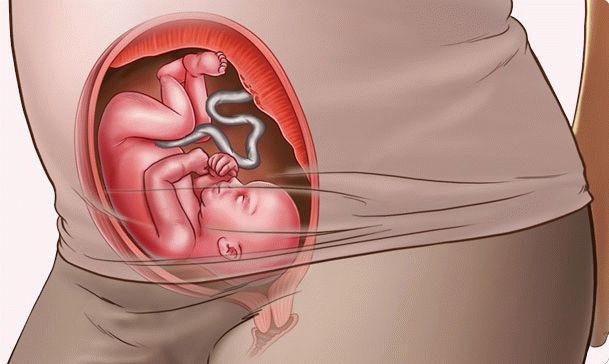

Les proportions du corps fœtal sont près de 100% proches des paramètres du nouveau-né. La seule différence est que le bébé a l'air mince, avec des bras et des jambes très fins et une peau ridée. En effet, la couche de graisse sous-cutanée n'est pas complètement formée.

Voici à quoi ressemble le fœtus à 24 semaines: